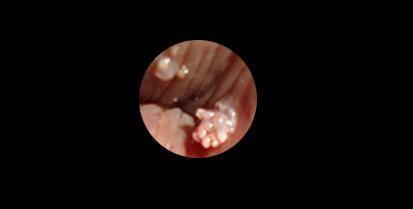

尖疣早期图片:

- 图片描述:阴茎表面可见多个菜花样赘生物,颜色为肉色或淡褐色,表面湿润,触碰易出血。

- 注意:尖疣通常呈簇状分布,数量较多,且可能逐渐增大。